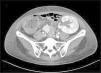

Seven months after the transplant, she was admitted due to a fever with respiratory symptoms lasting one month and macroscopic hematuria. Complementary exams revealed evidence of elevated inflammatory reactants, bicytopenia (anemia and leukopenia) and impaired kidney graft function. Bladder and kidney ultrasound was normal. We first interpreted the case as a respiratory viral infection with added bacterial superinfection, initiating broad spectrum and prophylactic empirical antibiotic treatment with trimethoprim/sulfamethoxazole given the sustained lymphopenia; in addition, we suspended MPA, maintaining the therapy with both immunosuppressants. In the absence of bacteriuria and negativity in the initial microbiological studies (urine culture, blood cultures, sputum culture, PCR of nasopharyngeal frotis for SARS-CoV-2, VRS and Influenzavirus A y B). We expanded the study with a thoracoabdominal computed tomography scan that showed splenomegaly and signs suggestive of nephritis in the renal graft (Fig. 1). The microbiological study was also expanded with respiratory smears and blood PCR for various viruses with positivity for Adenovirus (440,017 copies/mL), as well as its presence in urine (5,071,409 copies/mL), which confirmed HC secondary to Adenovirus. Given the persistence of fever and anemia-leucopenia even after the reduction of immunosuppression, we initiated antiviral therapy with cidofovir.